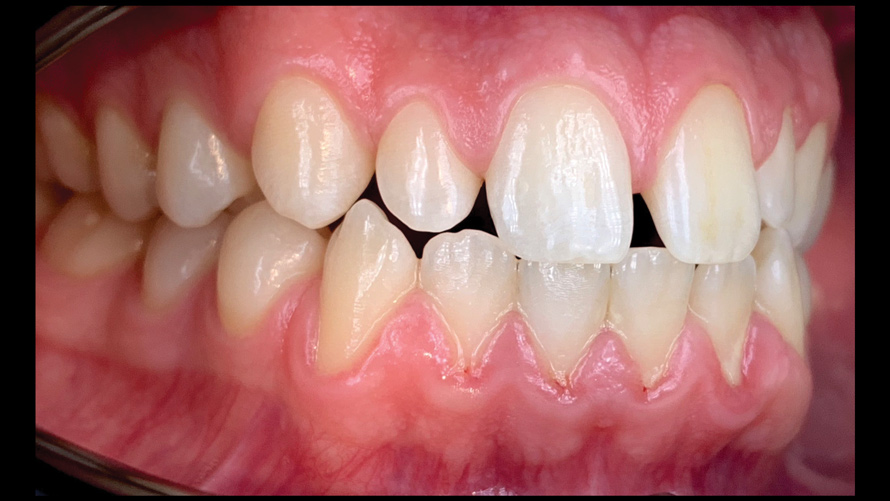

(9.) Preoperative esthetic case documentation using a smartphone and an EALS device.

Figure 9

(12.) Intraoral photographs taken with a smartphone and an EALS device for orthodontic evaluation.

Figure 12